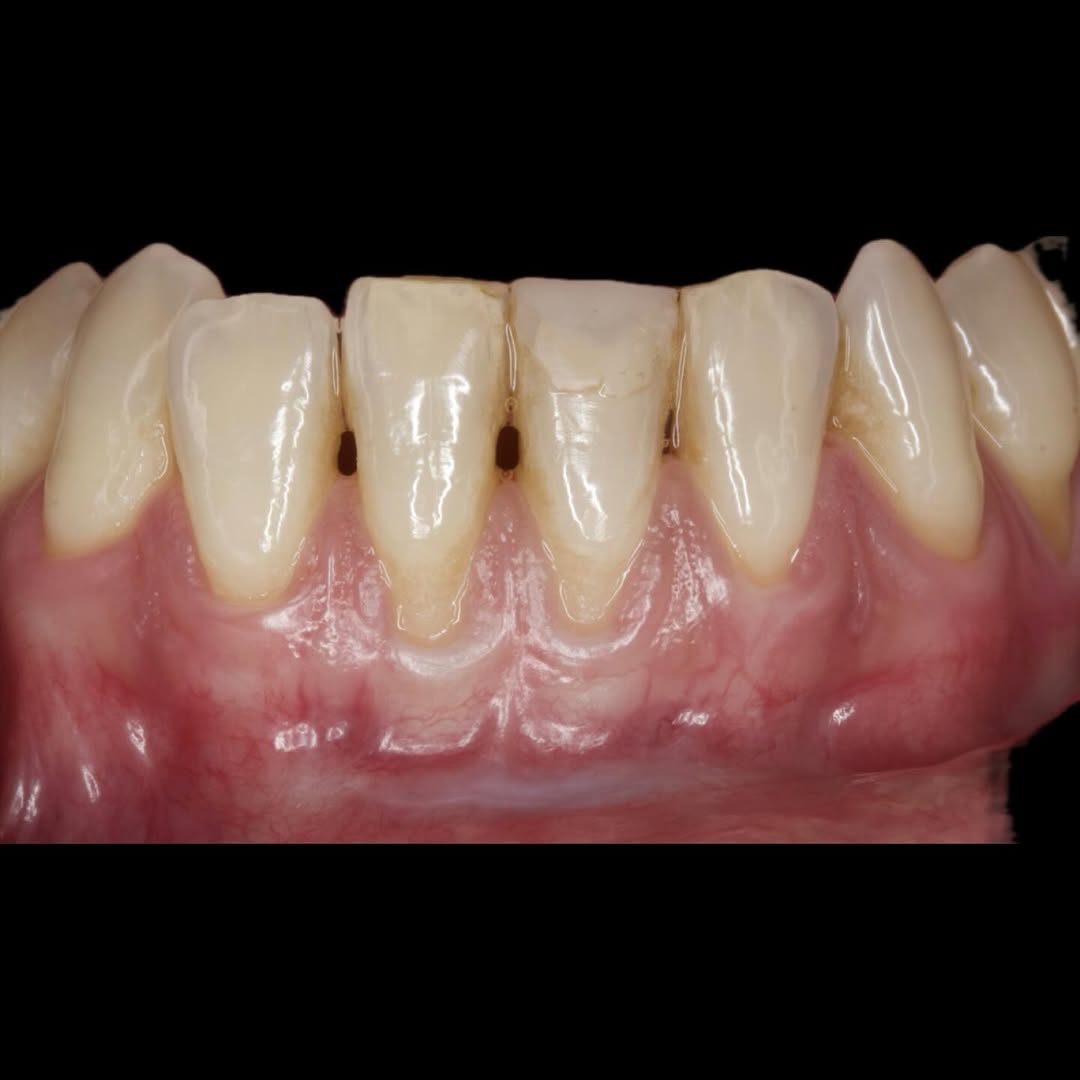

Hoy en día la Periodoncia es una de las áreas más importantes de la Odontología. En nuestro Centro de Formación te brindamos las mejores herramientas educativas y de capacitación necesarias para obtener el mayor provecho en el campo de la Odontología Estética y Restaurativa.

El objetivo del

Los problemas estéticos de una sonrisa no se ciñen sólo a los dientes eso lo sabemos todos. Por eso un curso de Perio-Estética, es fundamental para poder abordar casos de Estética y solo a través de un correcto diagnóstico previo podremos realizar un adecuado plan de tratamiento, muchas